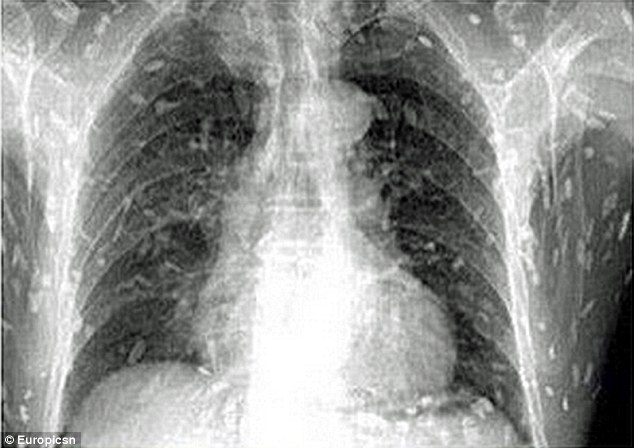

Kết quả chụp X-quang khiến anh chàng kinh hoàng thấy toàn bộ cơ thể mình bị nhiễm sán dây sau khi ăn quá nhiều sashimi – món cá sống cắt lát.

Phim chụp X-quang cho thấy sán dây làm tổ trong khắp cơ thể người đàn ông. |